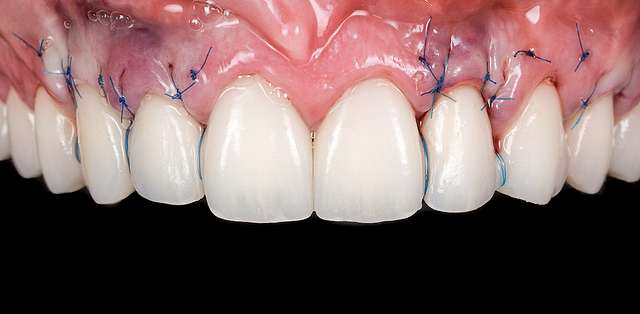

Grefa gingivala este o micro-chirurgie prin care se transplanteaza o mica bucata de tesut moale - gingie sau tesut conjuctiv (stratul intern al gingiei) pentru a acoperi un defect gingival. De obicei, acest tip de interventie este necesar pentru augmentarea implanturilor dentare, sau pentru a acoperi defecte cauzate de traume sau de afectiuni parodontale.Grefele se recolteaza din zona molarului de minte, sau de pe palat, si sunt transplantate in zona afectata.

Acesta interventie este una foarte delicata, lamele folosite pentru a efectua procedura sunt aceleasi folosite in oftalmologie, iar firele de sutura sunt si ele foarte fine. Firele se indeparteaza dupa 7-14 zile, in functie de caz, cand are loc vindecarea primara. Maturarea grefei dureaza aproximativ 90 zile, de aceea in momentul inserarii implanturilor preferam sa facem si grefa de tesut, pentru a sincroniza timpii de vindecare si ambelor proceduri.